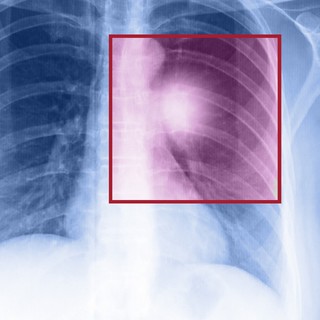

A mellkas CT (Thorax CT) egy számítógépes tomográfiás vizsgálat, amely részletes képeket készít a mellkas belső szerveiről, beleértve a tüdőt, szívet, ereket, légcsövet, nyirokcsomókat, bordákat és a környező szöveteket.

A mellkas CT, vagyis komputertomográfia egy korszerű, részletes képalkotó vizsgálat, amellyel az orvos a tüdőt, a szív környékét, a mellhártyát, a légutakat és a nagy ereket milliméteres pontossággal tudja megvizsgálni. A hagyományos röntgenfelvétellel szemben ez a vizsgálat háromdimenziós képeket készít, így olyan elváltozások is láthatóvá válnak, amelyek más módszerrel rejtve maradnának.

A CT-vizsgálat során röntgensugarakat használnak, amelyek különböző szögekből pásztázzák a testet, és számítógépes technológia segítségével háromdimenziós (3D) képeket állítanak elő. Ezek a képek sokkal részletesebbek, mint a hagyományos röntgenfelvételek, ezért a mellkas CT rendkívül hasznos a különféle tüdő-, szív- és mellkasi betegségek diagnosztizálásában és követésében.